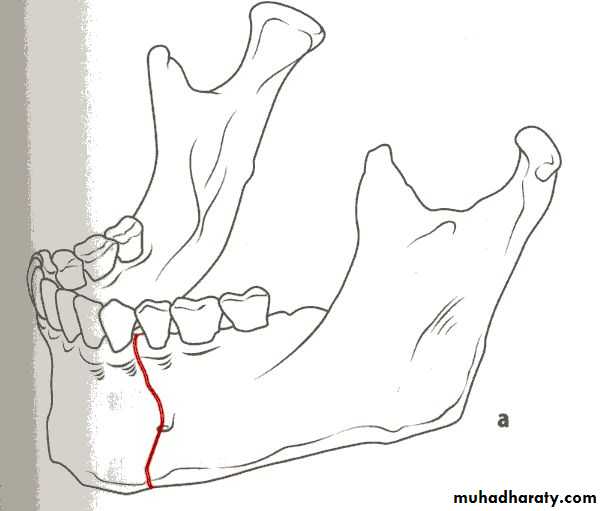

Class 34-classification according to the Direction of the fracture and favourability for the treatment

1- Horizontally favorable fracture.

2- Horizontally unfavorable fracture.

When the muscle pull resist fracture displacement , it is favorable(undisplaced), but, when the muscle pull distract the fragments away from each other resulting in displacement , it is unfavorable.

• Horizontally unfavorable fracture extends from the upper border downwards and backwards.

• Horizontally favorable fracture extend from upper border downwards and forwards.